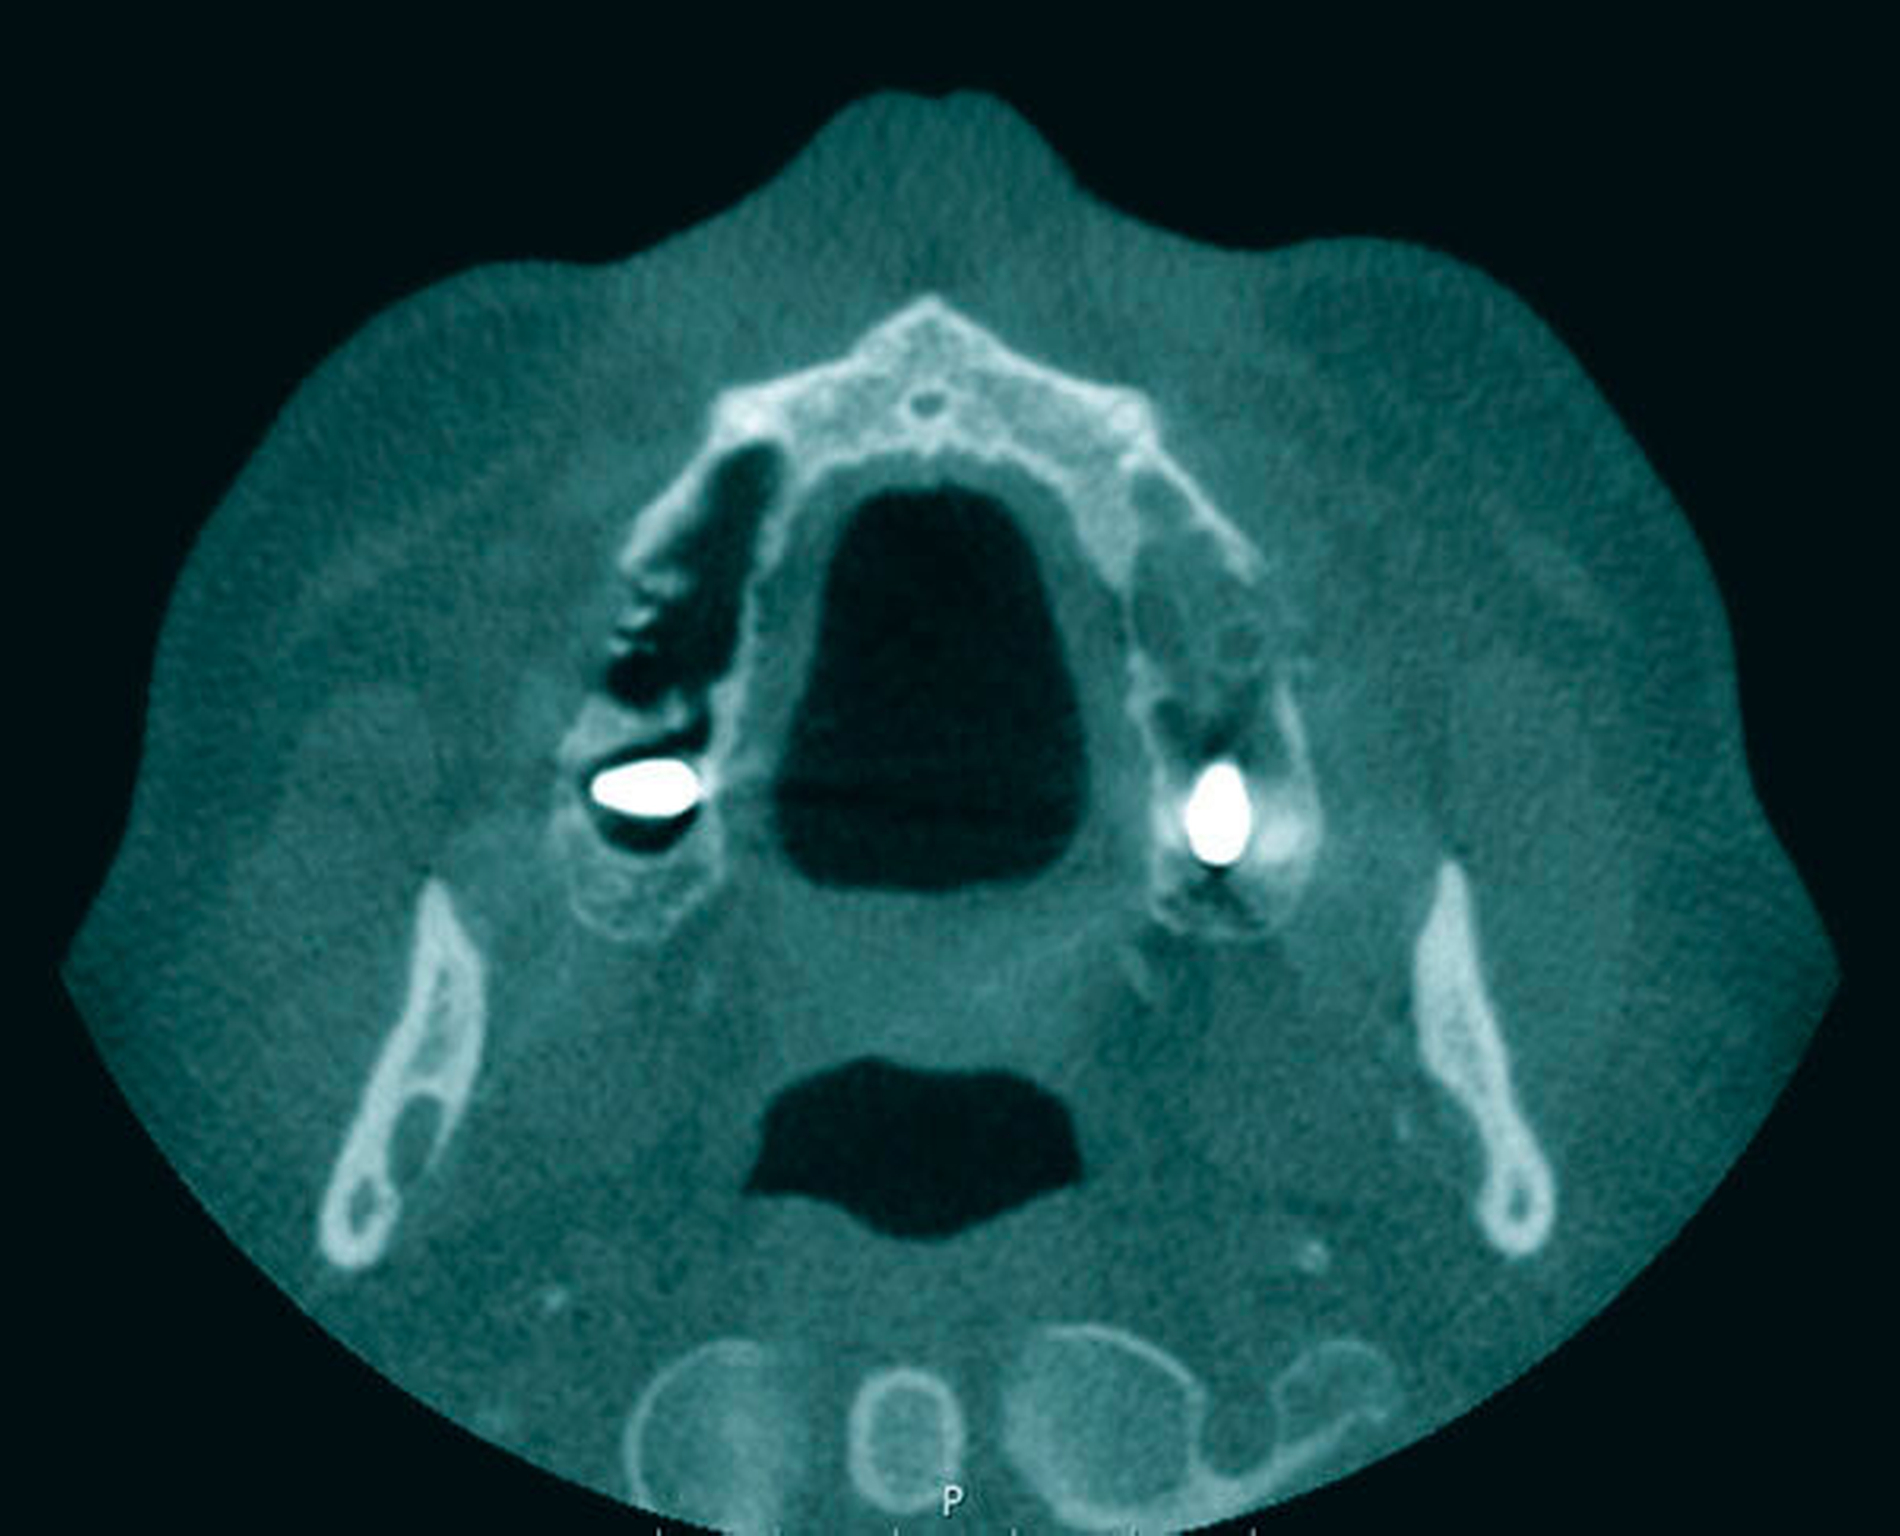

Zur weiteren Diagnostik und zur Beurteilung der Lage des Fremdkörpers wurde eine Digitalen Volumentomografie (DVT) durchgeführt. Diese bestätigte die Verdachtsdiagnose eines dislozierten Implantats im Bereich des Ostium naturale, wobei der Sinus maxillaris selbst Hinweise auf eine basale chronische Sinusitis aufwies (Abbildung 2).

Zur weiteren Diagnostik wurde auch hier eine DVT angefertigt, auf der sich in beiden Kieferhöhlen jeweils ein Implantat identifizieren ließ. Der linke Sinus maxillaris zeigte das Bild einer totalen Kieferhöhlenverschattung bei Verdacht auf Flüssigkeitsansammlung, die rechte Kieferhöhle wies keine Entzündungszeichen auf (Abbildung 6).